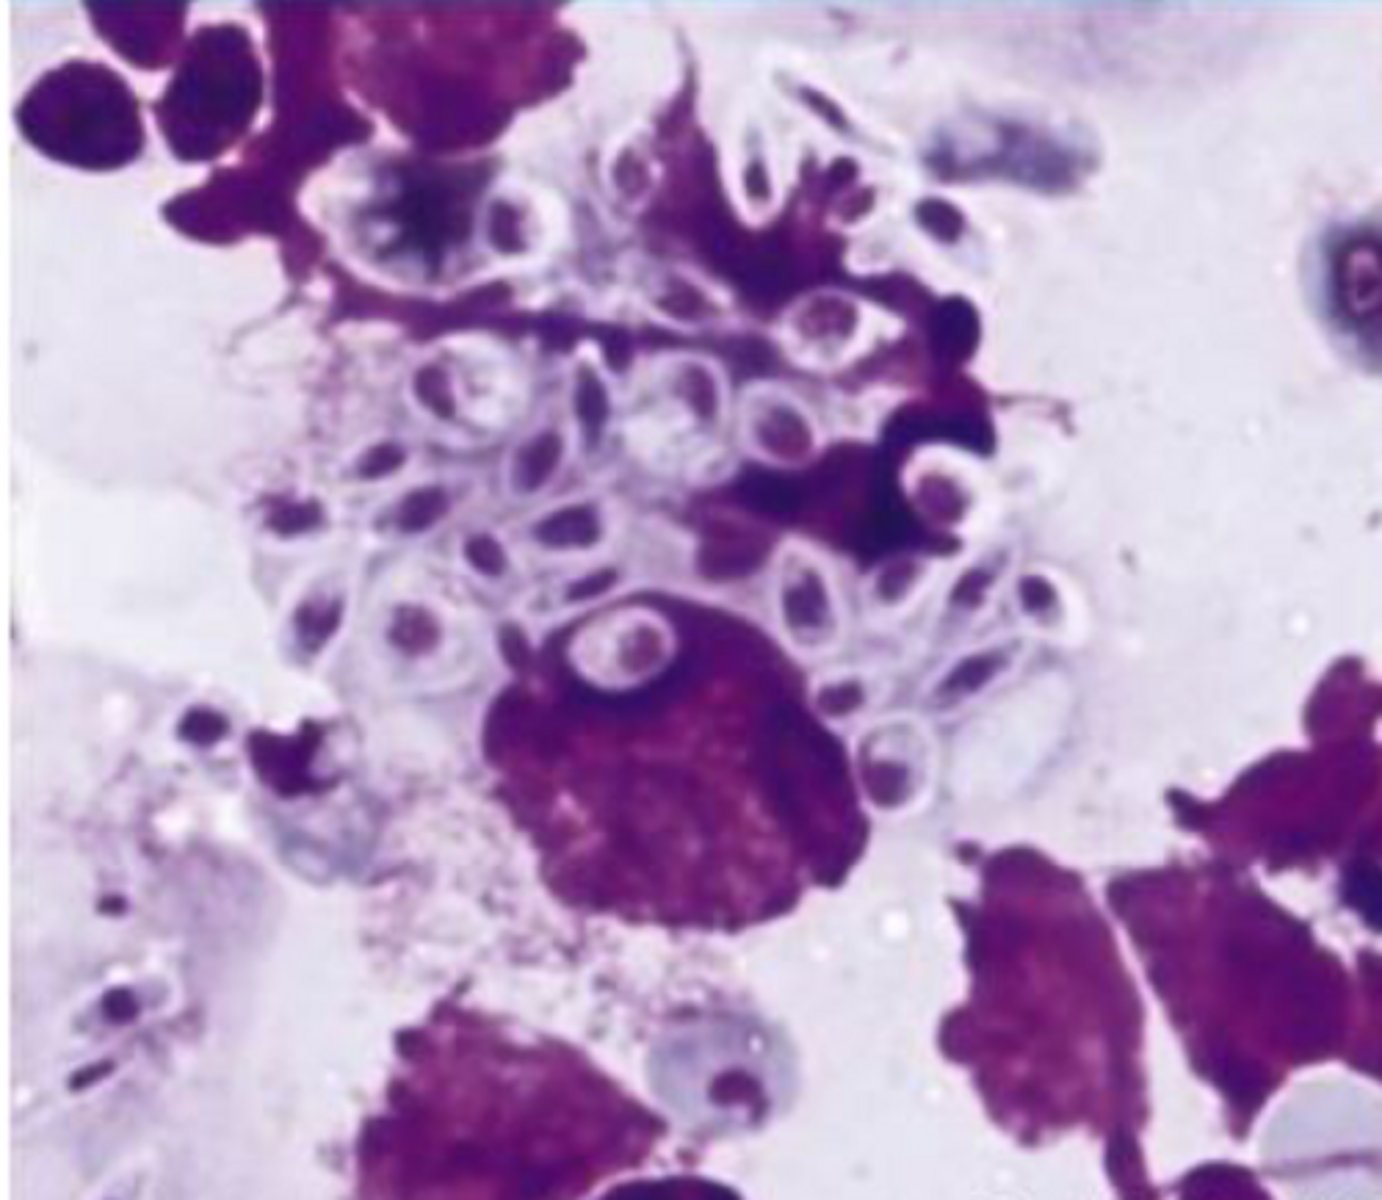

Identify the type of round cell neoplasia?

Transmissible Venereal tumor

-Face/ genitalia area